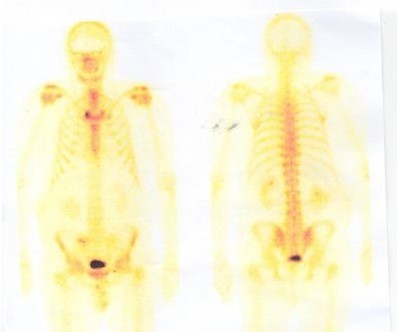

Muž 45 let – potíže s mikcí

Jste lékař urolog a přichází k vám pacient odeslán od praktického lékaře (PL). PL k Vám odesílá muže ve věku 45 let, pro nespecifické mikční potíže, které se objevily po prochlazení. Krev v moči pacient nepozoroval, lékařem to však nebylo došetřeno. Pacient nebyl doposud urologicky sledován, neléčil se.